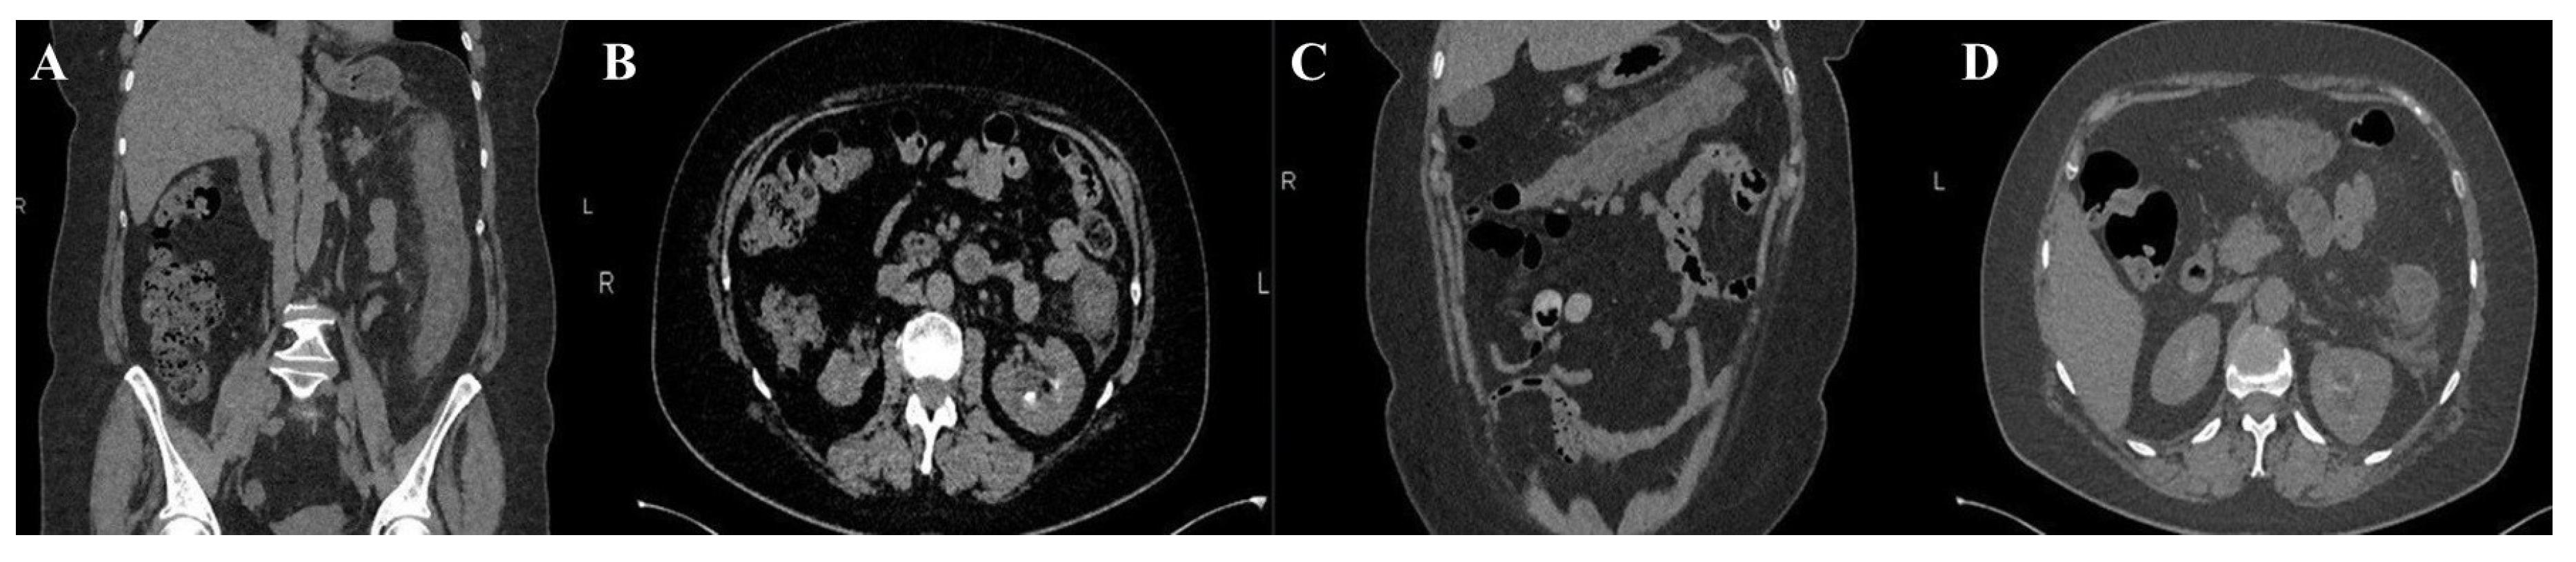

M, 59 | Pain, fever, bloody diarrhoea | Mild leucocytosis | E coli O157:H7 isolated in stool culture | Wall thickening through the entire colon at CT scan | Inflammatory pseudo-membranes, mucosal ischemia, and ulceration | Metronidazole Surgical intervention |

| Tominaga, 2014 (15) | M, 81 | Pain, febrile, bloody diarrhoeae, | Inflammatory syndrome, thrombocytopenia | E coli O157 isolated in stool culture; positive verotoxin | Thickening of the entire colon wall and ascites at CT scan | haemorrhagic necrosis into mucosa with subjacent oedema | Cefotiam, levofloxacin Surgical intervention |

| Radhakrishnan, 2019 (16) | M, 17 | Pain, fever, bloody diarrhoea | Mild leucocytosis, | Positive STEC antibodies | Wall thickening in the ascending colon at CT scan | Haemorrhagic lesions, inflammatory exudate, and atrophic crypts | Cefuroxime, metronidazole, Eculizumab | Yes | Thrombocytopenia, partial-complex seizures |

ND | Superficial mucosal necrosis, haemorrhages into lamina propria | Ciprofloxacin, metronidazole, piperacillin-tazobactam, | No | No |

Moderate leucocytosis | E coli O111 isolated in stool culture | Severe colitis, without evidence of large vessel occlusion on CT angiogram | Ischemic colitis in appearance | Ceftriaxone, metronidazole | No | No |

Mild inflammation (CRP) | GI panel stool positive for STEC O157 | Thickened wall of terminal ileum at angio-CT | Inflamed and ulcerated mucosa | Azithromycin | No | No |

| Al-Smadi, 2023 (7) | M, 21 | Pain, afebrile, bloody diarrhoea | Mild leucocytosis | Positive stool for STEC | Normal CT scan of large intestine | Erosion and necrosis of mucosa, crypt atrophy | Ceftriaxone, metronidazole | No | No |